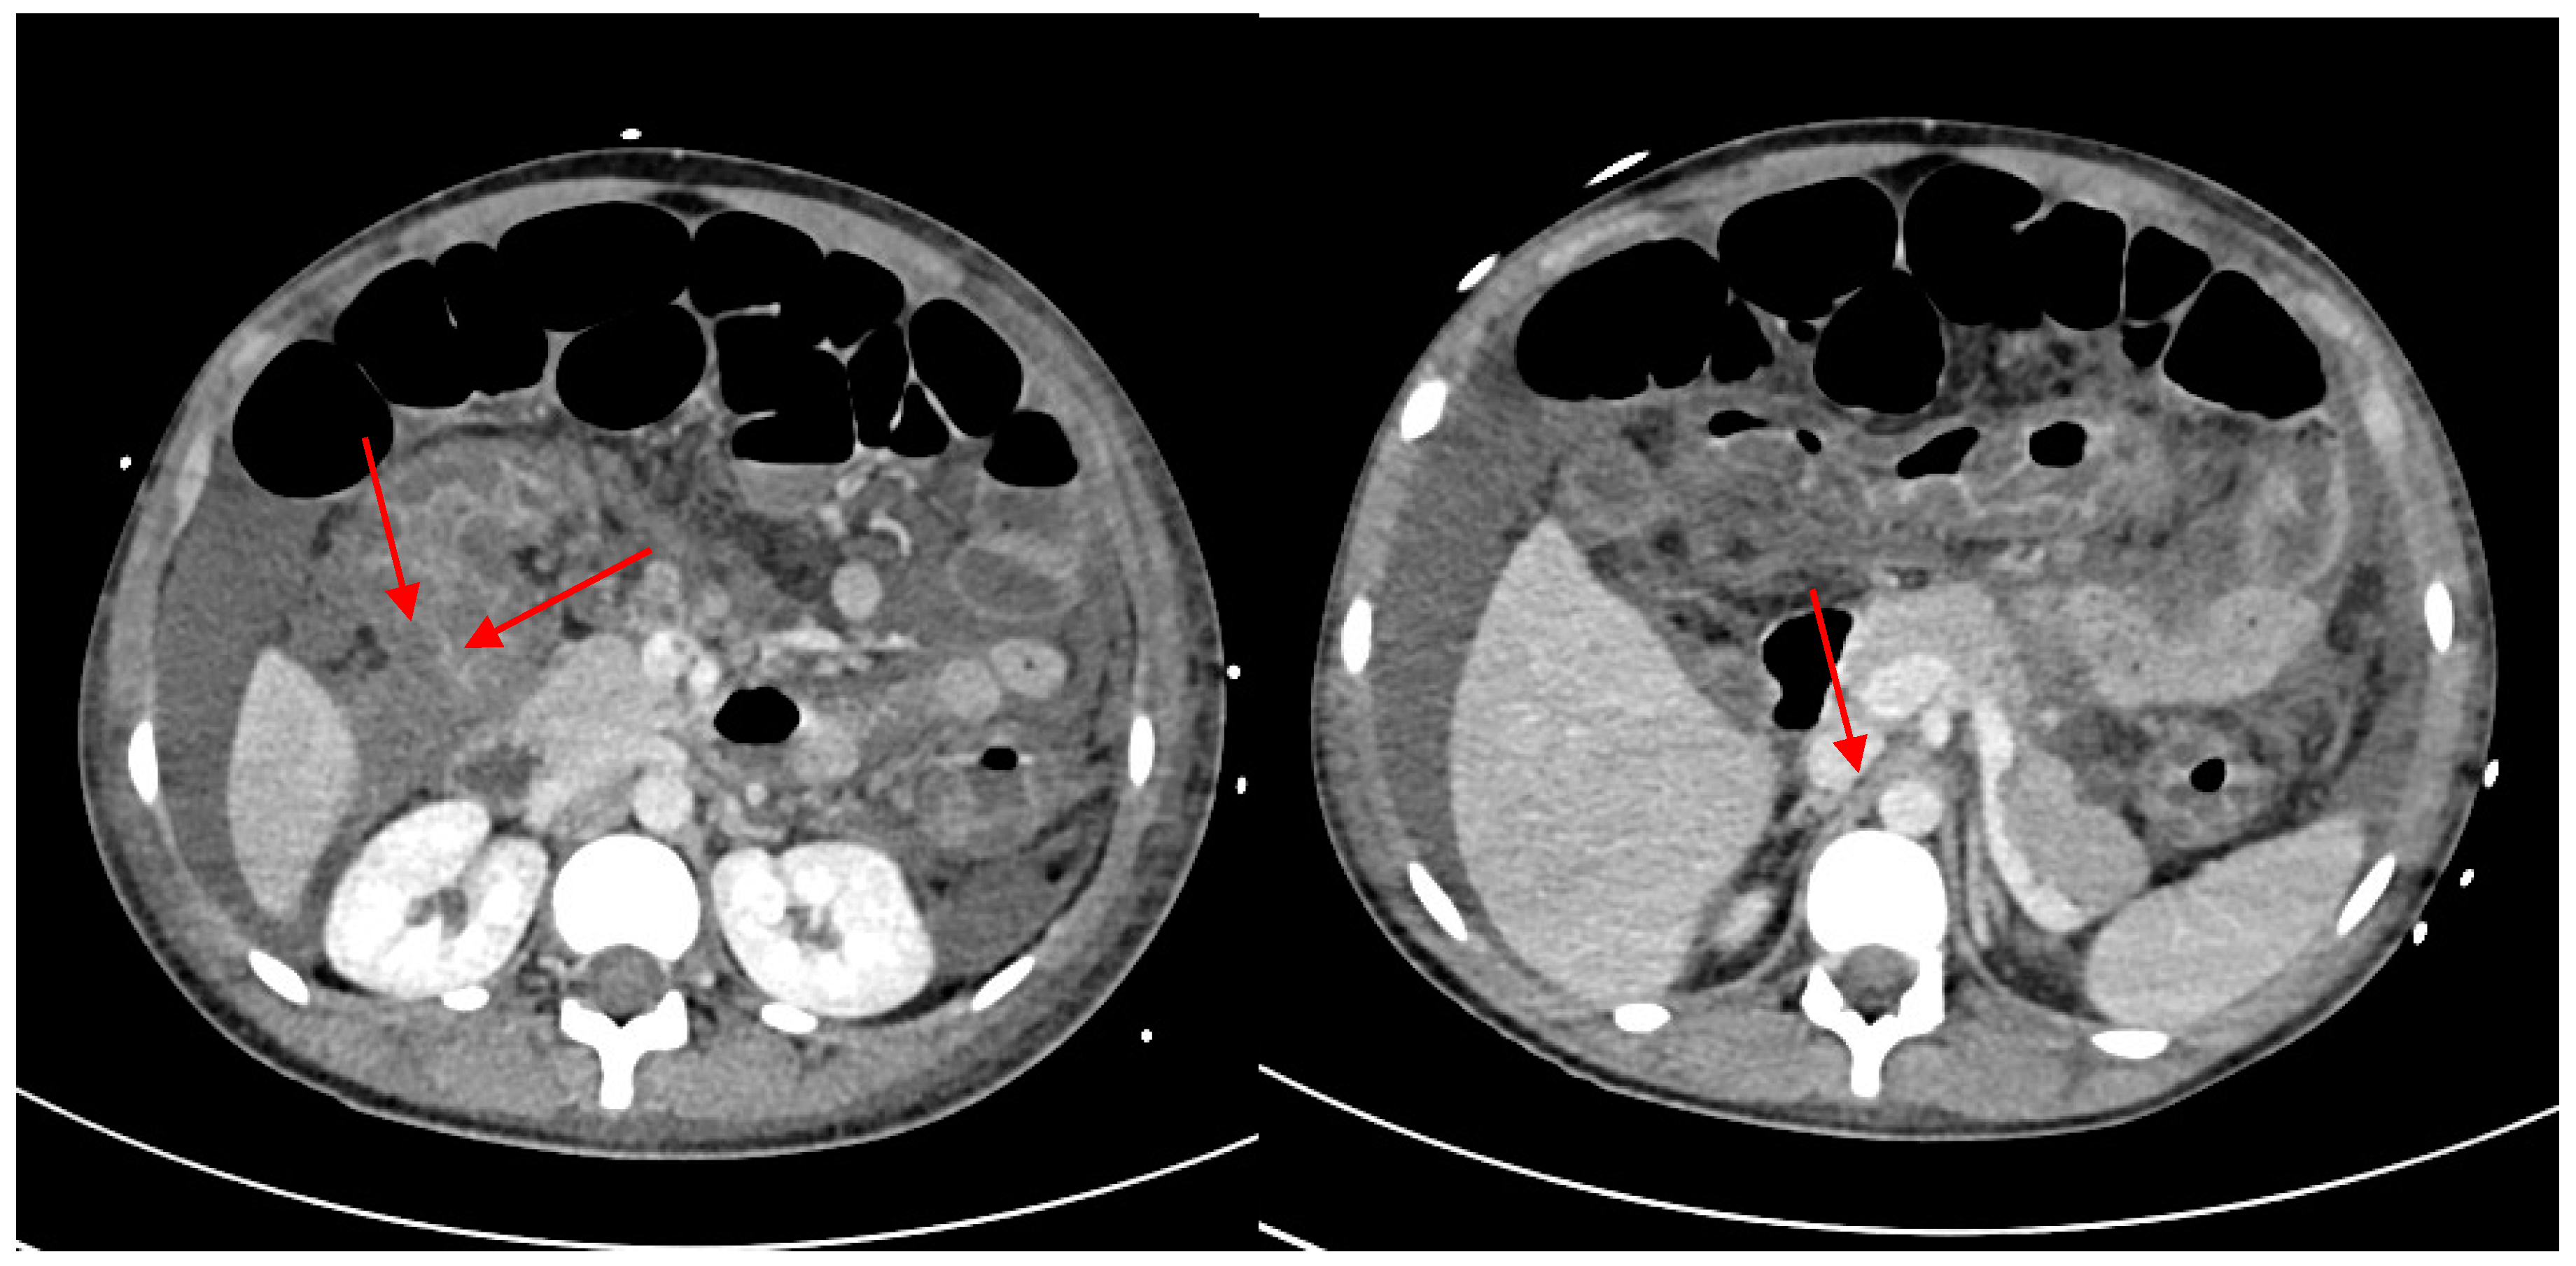

2. Case Description